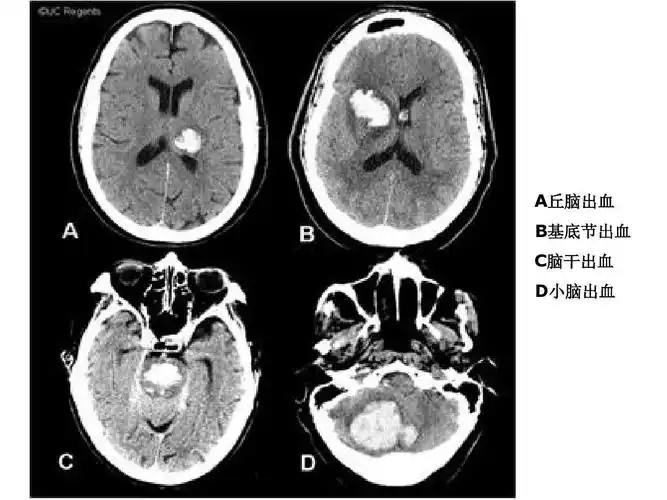

医学影像学 头颅 诊断 ct 头颅ct解剖及诊断 a丘脑出血 b基底节出血 c